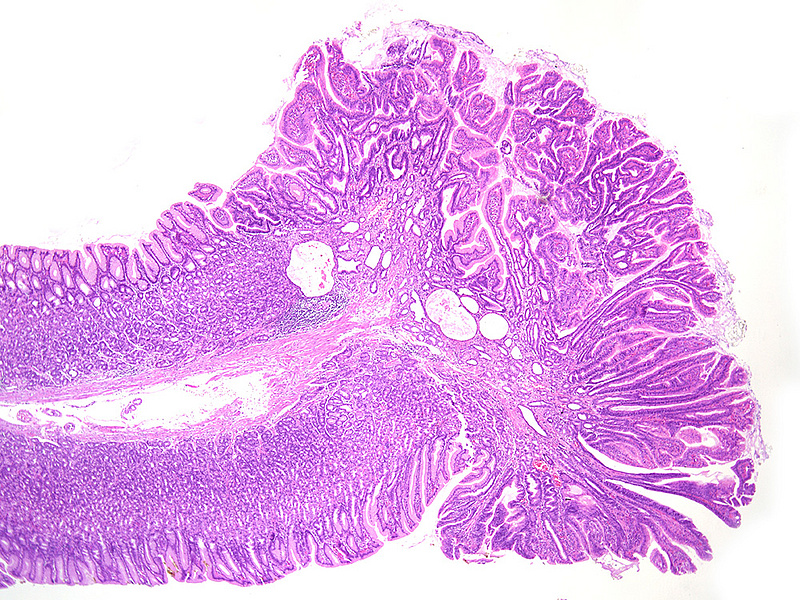

Three polyps, measuring from three to eight millimeters in maximum diameter, were incidentally discovered within the oxyntic mucosa of 59-year-old female and removed by cold snare polypectomy. There was no history of familial adenomatous polyposis (FAP), gastric adenocarcinoma and proximal polyposis of the stomach (GAPPS), or other inherited syndrome, as well as no personal or family history of cancer.  No usage of PPI. The background mucosa was normal on gross inspection.

Upon histology, the three polyps showed a similar morphology. The polyps demonstrated irregularly shaped, branching, papillary projections with well-vascularized stroma (Panels A-C). On higher magnification, these projections were lined by dysplastic columnar cells, with hyperchromatic, enlarged and stratified nuclei and a distinctive apical mucin cap, prompting diagnosis of foveolar-type gastric adenoma with low-grade dysplasia (Panels D-F). The background tissue showed non-atrophic oxyntic mucosa, without gastritis, Helicobacter pylori infection or intestinal metaplasia. In summary, the histology was consistent with the newly described variant of foveolar-type adenoma with a raspberry-like appearance.